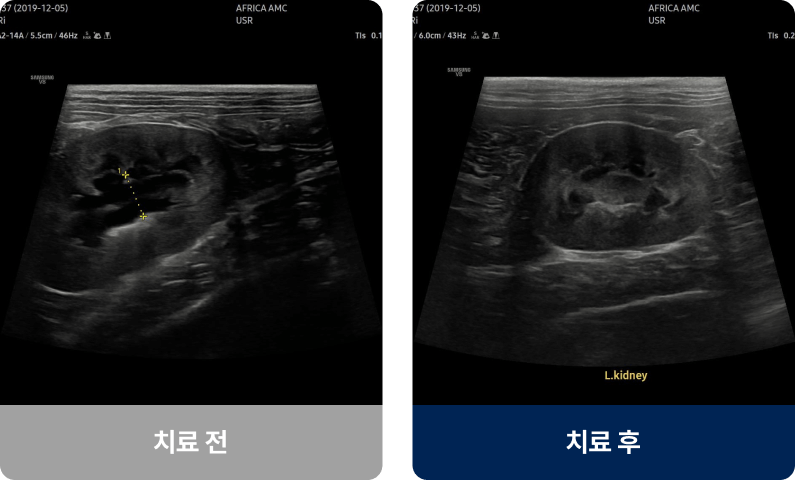

신장센터는 신장의 여과 기능 이상과 요로계 질환을 진단·치료하는 분야입니다. 아프리카 동물의료센터는 신장 전문 의료진이 정밀 검사를 통해 장기 기능을 보호하는 맞춤형 치료 계획을 제공합니다.

아프리카 동물의료센터는 신장 전문 의료진이 정밀 검사를 통해 장기 기능을 보호하는 맞춤형 치료 계획을 제공합니다.